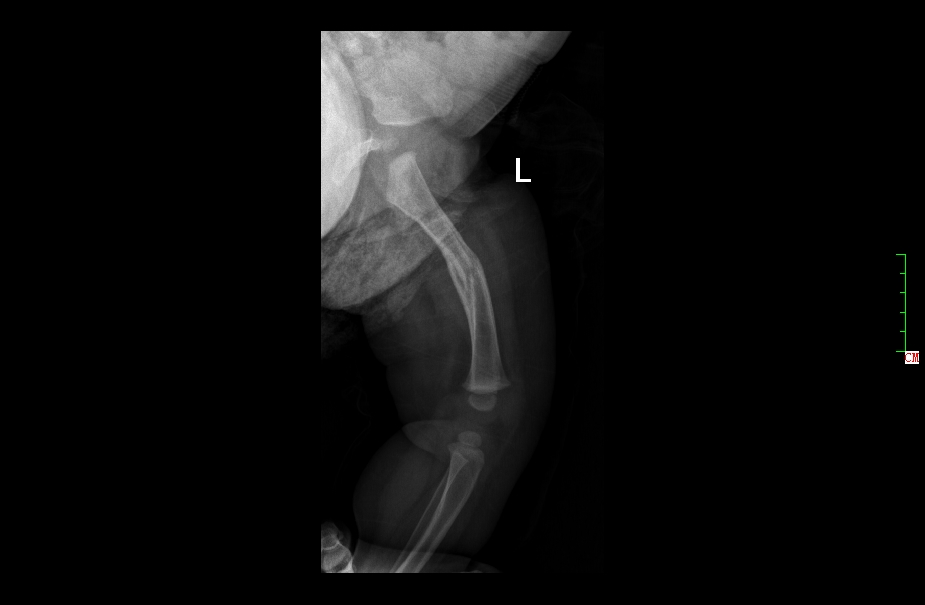

与成人相比,小儿骨折愈合能力强,速度快,再塑形能力强。因此,儿童骨干部骨折如果力线符合原则,纠正旋转和缩短移位,即使有一些错位,也能随着生长发育矫正而不留任何后遗症。对于骨干部的骨折一味追求对齐而进行反复复位,骨折的断端可能会引起局部血管和神经损伤,得不偿失。但是对于儿童骨干骨折,除了不片面扩大手术及内固定治疗适应症外,也不能过分依赖生长塑形。

2 月后复查正位片

2月后复查侧位片

1年后复查正位片,已完全愈合,自行矫形至正常